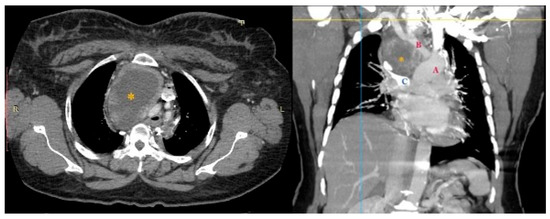

The performed contrast-enhanced computerised tomography (CECT) of the chest revealed a large, well-defined, centrally necrotic, peripherally enhancing mass lesion in the superior mediastinum extending to the anterior mediastinum. There was displacement of the trachea to the left side, compression of brachiocephalic veins and proximal SVC, and a possibility of sclerotic skeletal metastasis in the vertebrae (Figure 2). A CT-guided biopsy was planned, and a fluorodeoxyglucose (FDG) positron emission tomography (PET) scan (SUV-13.1) was performed to differentiate between a malignancy or a mass with an infective lesion and to look for metastasis. The scan revealed a large 10.7 × 6.5 × 6.2 cm well-defined mass lesion of neoplastic aetiology with a mass effect—likely of thymic origin, but with no evidence of metastasis (Figure 3).

Figure 2.

CECT showing large central necrotic lesion measuring 8.4 × 6.1 × 8.2 cm involving the superior mediastinum, displacing the trachea to the left, and compressing the brachiocephalic veins and the proximal SVC. * necrotic lesion.